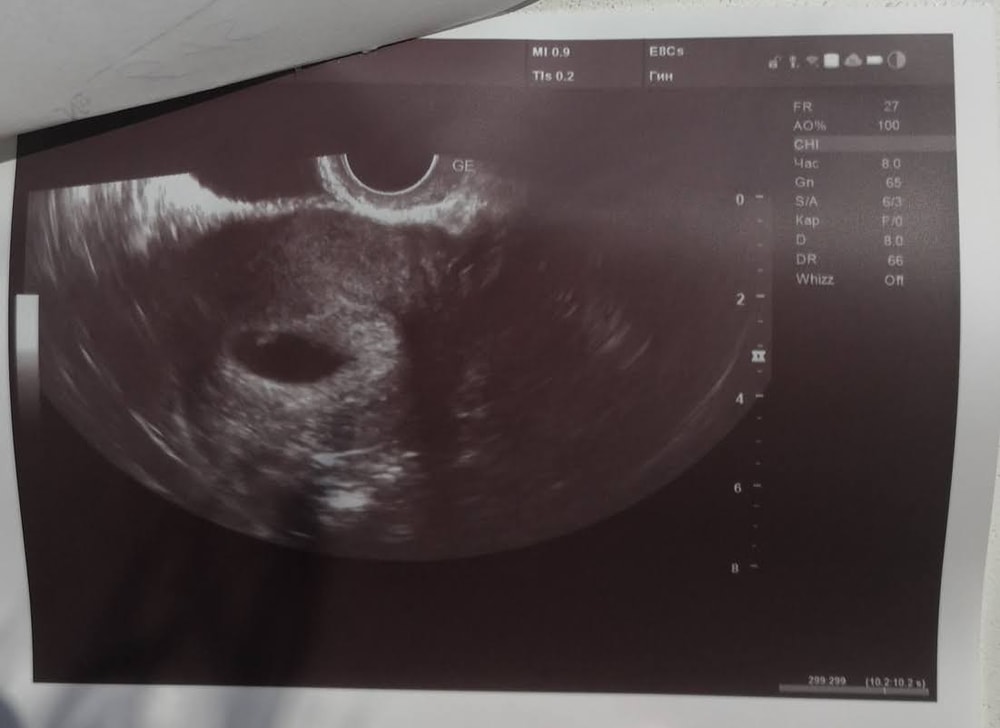

Честно говоря, очень мало похоже на Б (по крайней мере на фото из моего УЗИ так Б не выглядела).

Это УЗИ на 23 день задержки

Не знаю, бывает, что врачи путают кисту с Б, но больше вероятности, что просто киста вырастает вместе с Б на фоне гормонального сбоя. На Вашем фото я бы сказала, что это киста, да и врач бы про Б сказала бы, если б увидела. А вот на фоне чего она выросла... Либо просто, либо Б появится потом.